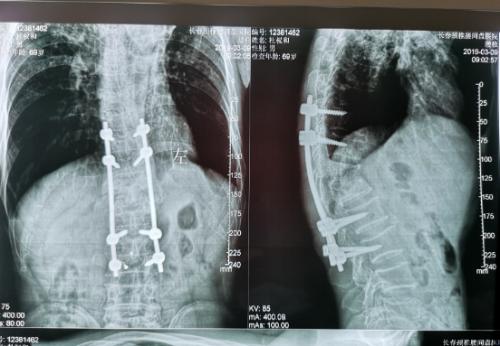

在长春市传染病医院骨科·普外科的走廊里,王大爷和老伴握着医生的手万分感激。光看他的脸色与精神,很难想象他曾经还是一位有下肢瘫痪的骨结核患者,结核杆菌在他的胸椎上肆虐大半年之久,侵蚀了多个椎体。但这一切已成为过去,在骨科·普外科全体医护人员的努力下,已经可以像正常人一样行走了。所幸的是,长春市传染病医院成功为其实施了脊柱畸形矫正、椎体结核侧前方减压灶清除椎间植骨术,为王大爷解除了疾痛,长春市传染病医院的手术是省内此类手术的领先水平。

经过检查,罗坚主任凭着丰富的临床经验初步认为王大爷患的是胸椎结核伴脊髓压迫症,那么是什么原因造成的?通过脊柱磁共振检查,罗主任发现王大爷患胸椎脊髓压迫的元凶正是“骨结核”。王大爷胸椎骨7-11节被结核杆菌严重侵蚀,在重体力活后,胸椎脊髓神经受到压迫,最终导致下肢瘫痪。同时患者双肺结核伴左上叶不张,左侧胸腔大量积液。如果等待双肺结核治愈,需时日很长,脊髓的受压如果不能及时解除,导致脊髓变性,那么瘫痪就难以恢复了,在积极治疗肺结核胸腔积液引流,罗坚主任为王大爷尽快安排实施手术。

手术过程中,病人腰大肌脓肿巨大,病椎破坏重游离死骨多,结核物质使脊髓严重受压,既要侧前方减压清除病灶,又要完成后凸畸形的矫正,再由于王大爷年龄较大、体质差,风险高,对技术与手术期管理都是很大的挑战。

罗坚、陈松峰和任重三位医师组成的团队实施手术。罗坚主任凭借其多年外科生涯中大量胸椎结核手术所积累的丰富经验,在脊柱侧前方减压,病灶清除、植骨和后凸畸形矫正胸膜外操作。手术按计划顺利完成,而辗转数家医院的“求医记”终于告一段落,在外等候的家人听到手术成功的消息后喜极而泣。